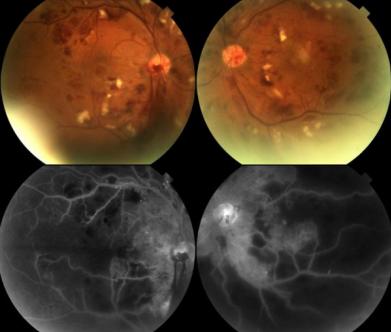

图2 首次就诊时的放射性视网膜病变。上方眼底彩照显示双侧视网膜显著缺血性改变。荧光血管造影显示出血遮挡荧光以及毛细血管无灌注区。

图3 放射性视网膜病变激光治疗前。上方的彩照显示放射性视网膜病变加重,双侧视乳头新生血管导致玻璃体出血。视网膜严重缺血。